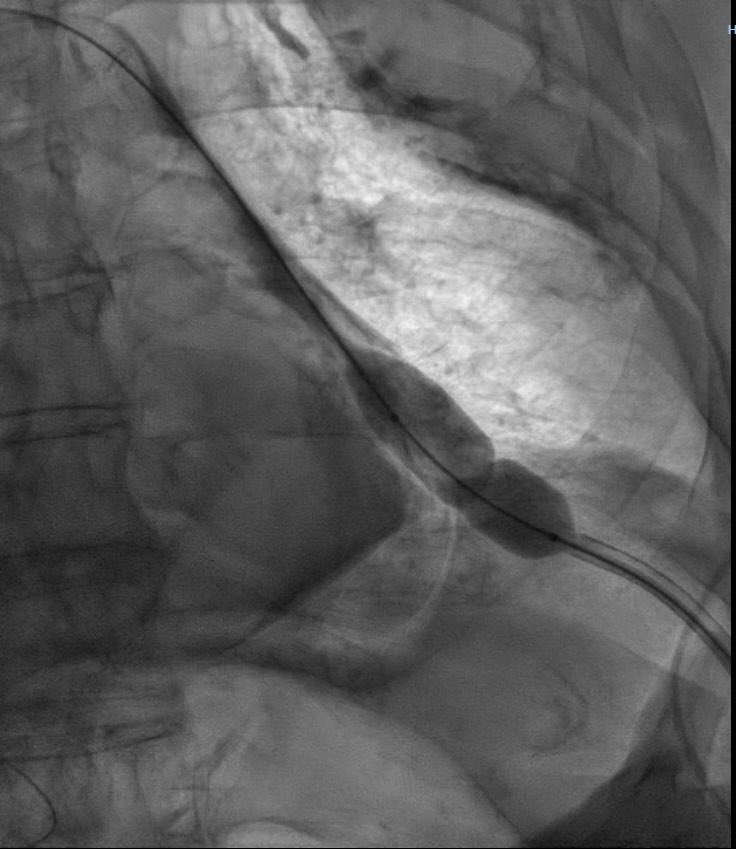

La pericardiotomia con balón es una alternativa a la ventana pericárdica quirúrgica en pacientes con derrame recidivante.

1

11

43